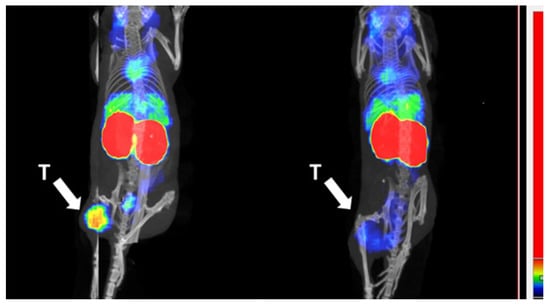

3.5. Biodistribution in Tumor Bearing Mice